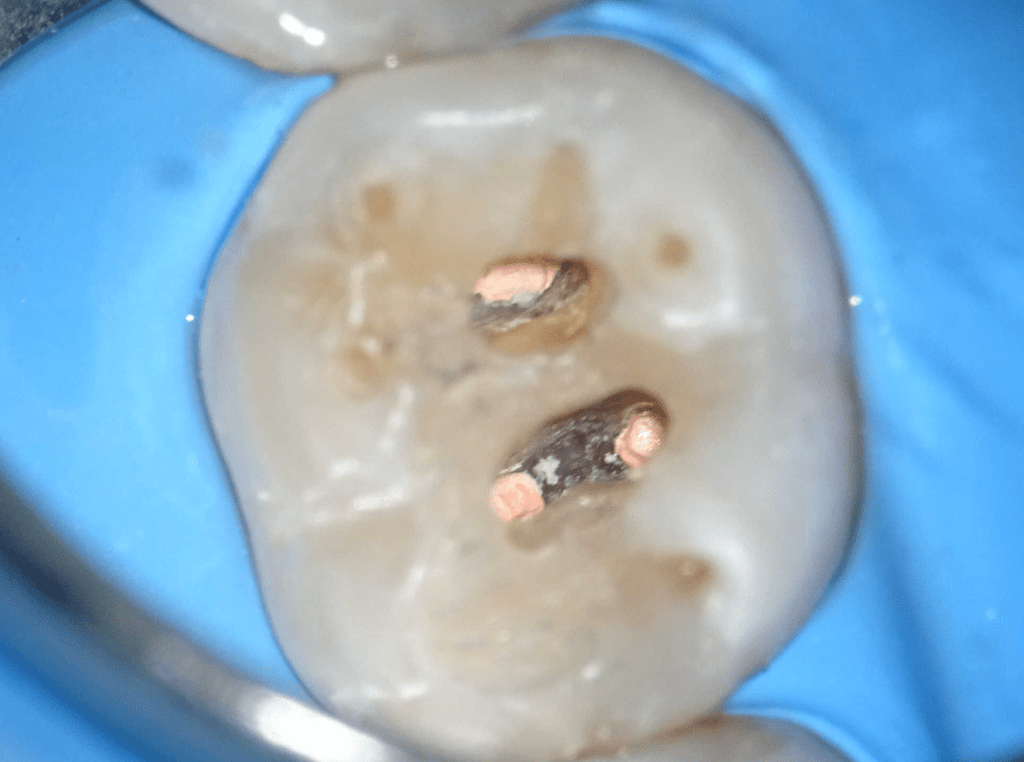

Fisura, remoción amalgama para explorar